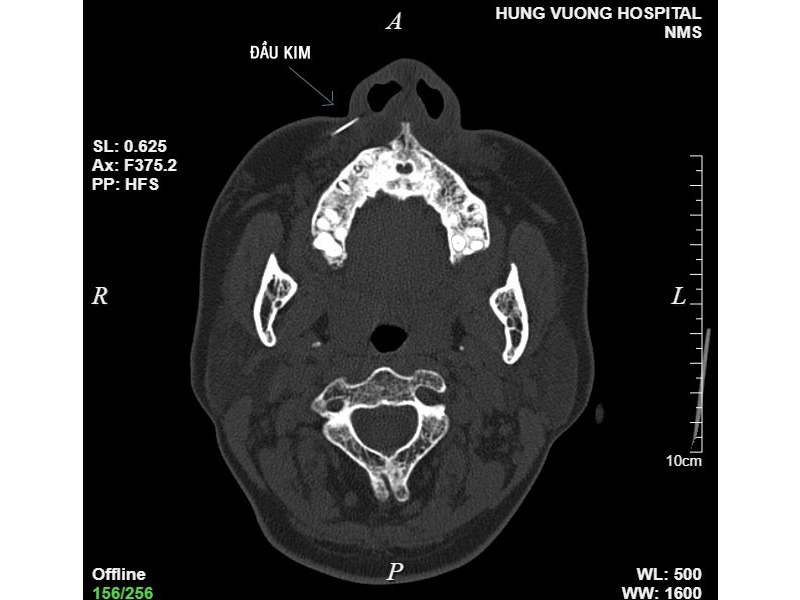

Sau khi thực hiện chụp CT, kết quả cho thấy hình ảnh dị vật khoảng 1cm vị trí phần mềm cánh mũi phải. “Vị trí kim găm sâu vào má, bệnh nhân được bác sĩ chỉ định thủ thuật lấy dị vật”. Sau 10 phút, dị vật là đầu kim đã lấy ra từ vùng má bệnh nhân.